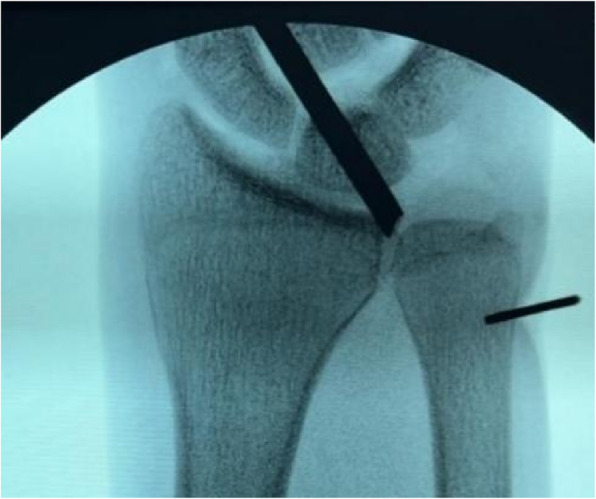

A 2-cm longitudinal incision was made along the ulnar border of the wrist, proximal to the ulnar styloid. Under fluoroscopic guidance, a single horizontal transosseous tunnel (1.2 mm in diameter) was drilled at the ulnar neck level, proximal to the physis and directly beneath the fovea, ensuring complete avoidance of the physis to prevent growth disturbance (Fig. 1, suggested schematic of bone tunnel location).

Fig. 1.

Under fluoroscopic guidance, a single 1.2-mm horizontal transosseous tunnel was drilled at the ulnar neck level, proximal to the physis and directly beneath the fovea to ensure complete avoidance of the physis and prevent growth disturbance. The X-ray image shows the positioning of the transosseous tunnel at the ulnar neck level